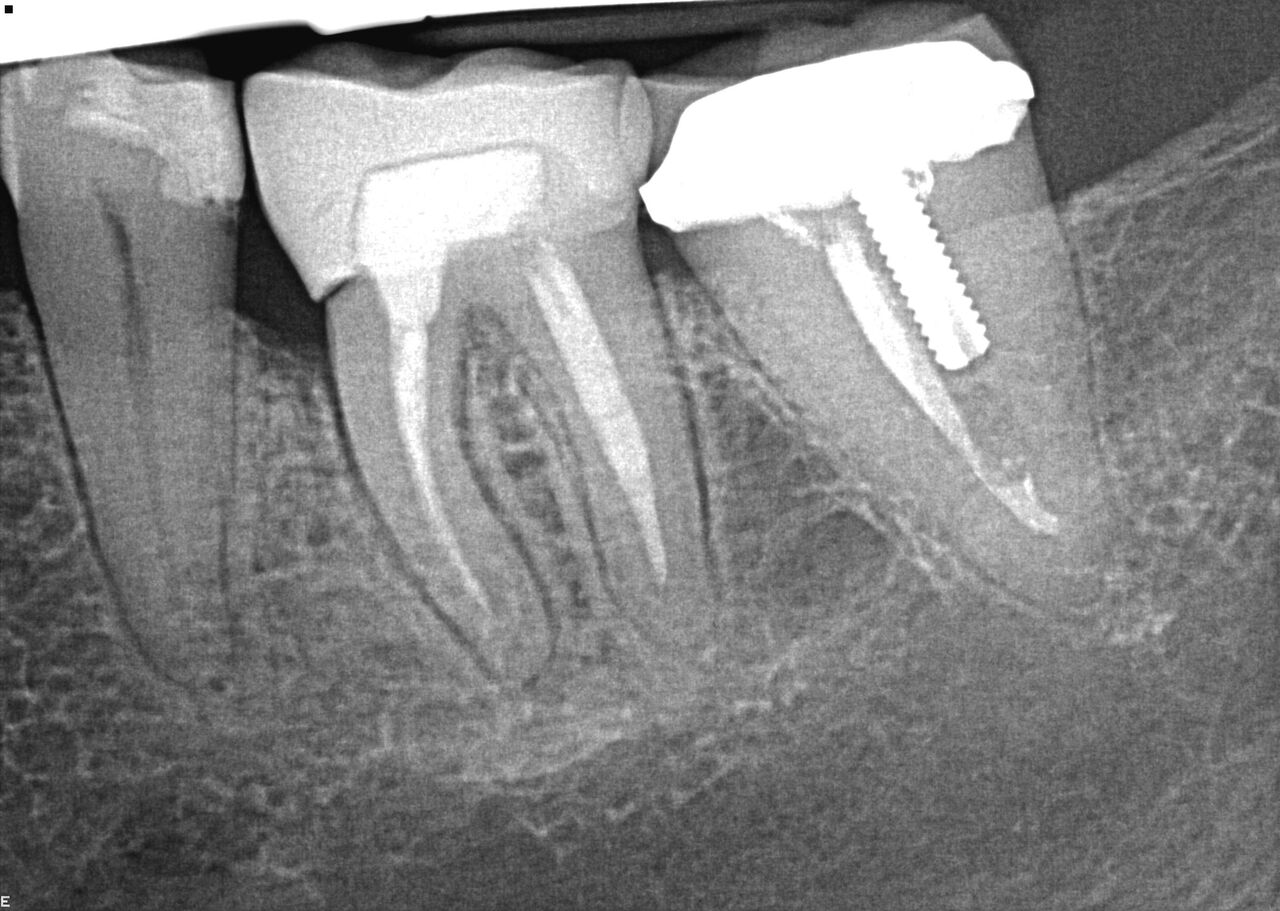

(8.) Case 2 initial radiograph of Nos. 12 through 14 with disunion of No. 12 crown to underlying root.

Figure 8

( 9.) Case 2 initial radiograph of Nos. 12 through 14 with disunion of No. 12 crown to underlying root.

Figure 9

A 67-year-old woman presented on an emergency basis with a bad odor and taste from crown No. 12, which had been diagnosed that day at hygiene recall as decayed and no longer attached to the underlying root (Figure 8 and Figure 9). The patient was anesthetized and the existing bridge was sectioned (Figure 10), leaving crown No. 14 intact. The No. 12 root was extracted and the site was fully debrided of granuloma. A platform shift implant was stabilized in excess of 45 Ncm in position No. 12, which was prosthetically correct. The soft tissue of pontic site No. 13 was contoured to mimic soft tissue contours of a bicuspid and an implant was secured in excess of 45 Ncm. Implant No. 13 was milled to allow for unimpeded seating of the temporization abutment, whereas implant No. 12 did not need milling as it was a platform-shift implant. The existing crown No. 12 and cantilever No. 13 were revised to be a temporary bridge on Nos. 12 and 13 (Figure 11 and Figure 12). The revised temporary bridge was positioned in infraocclusion and cemented after the extrusion of excess cement extraorally (Figure 13). No bone graft or sutures were placed as the temporary crowns sealed the sockets.

The patient was prescribed antibiotics and analgesics and instructed in postoperative care particular to immediately provisionally restored implants. At 6 months, integration was confirmed (Figure 14) and the patient returned to her dentist for restoration. The implants were restored with individual cement-retained crowns with a platform shift for No. 12 restoration from the 6-mm diameter of the implant to a 5-mm diameter of the final restoration (Figure 15 and Figure 16).